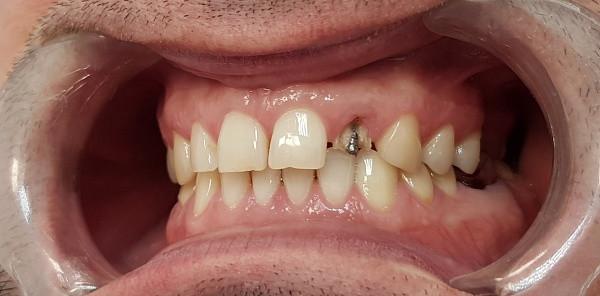

Пациент, 42 года, обратился с жалобами на эстетические проблемы. Для улучшения внешнего вида его верхней челюсти были установлены коронки из диоксида циркония, которые отличаются повышенным гарантийным сроком службы. Подробнее о материале и его свойствах вы можете узнать на персональной консультации.